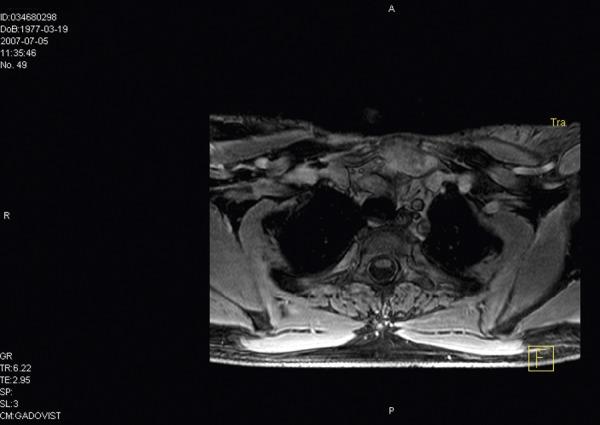

胸内硬纤维瘤的多学科治疗:病例系列和叙述性综述。

Multidisciplinary treatment of intra-thoracic desmoid tumors: case series and narrative review.

Primary intra-thoracic desmoids are exceedingly rare borderline tumors, with 34 reported cases in the English-language literature. The characteristic localized infiltrative growth and the high rate of recurrence can result in life-threatening conditions. Radical surgical resection is considered to be the primary treatment. Achieving negative surgical margins is a challenge. Cases with positive surgical margins are associated with a high rate of local recurrence; therefore, other multimodal approaches play a large role in their therapy.

CASE REPORTS

The authors reviewed the relevant literature and presented examples of long-term follow-up of 3 intra-thoracic desmoid tumour patients, multidisciplinarily treated between 2000 and 2008. All reports of intra-thoracic desmoid tumors that the authors could find on PubMed or in the reference sections of these PubMed located articles were included using the search terms: intra-thoracic, desmoid, aggressive fibromatoses.

原发性胸内硬纤维瘤是一种极为罕见的交界性肿瘤,英文文献中有 34 例报道。其特征性的局限性浸润性生长和高复发率可导致危及生命的情况。根治性手术切除被认为是主要的治疗方法。达到阴性手术切缘是一个挑战。阳性手术切缘的病例与高局部复发率相关;因此,其他多模式方法在其治疗中起着重要作用。

病例报告

作者回顾了相关文献,并介绍了 3 例胸内硬纤维瘤患者的长期随访情况,这些患者于 2000 年至 2008 年间接受了多学科治疗。作者使用以下检索词在 PubMed 或这些 PubMed 定位文章的参考文献部分搜索了所有能找到的胸内硬纤维瘤报告:胸内、硬纤维瘤、侵袭性纤维瘤病。